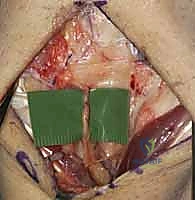

- Extensor Retinaculum Division: Now, we'll identify the extensor retinaculum. I'm dividing the retinaculum directly over the third extensor compartment, releasing the extensor pollicis longus (EPL) tendon. This allows us to mobilize the EPL radially, providing better access to the underlying capsule.

TECH FIG 3 • A. Dissection of septa to create ulnar-based flap of extensor retinaculum.

* Developing Retinacular Flaps: Next, we'll develop ulnar-based flaps of the extensor retinaculum. This involves carefully dividing the septa that separate the third, fourth, and fifth extensor compartments. Use a fine Metzenbaum scissors or a scalpel with a #15 blade to meticulously incise these septa. This maneuver allows us to reflect the retinaculum ulnarly, exposing the dorsal wrist capsule more broadly.

TECH FIG 3 • B. Preparing to reflect extensor retinaculum.

TECH FIG 3 • C. Retinaculum has been reflected ulnarly and extensor tendons are released.